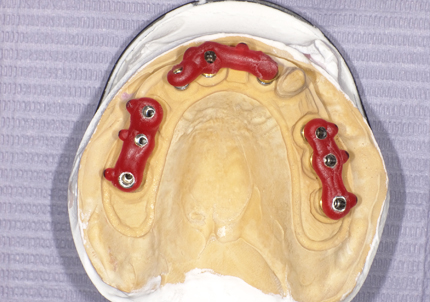

7.サージカルガイドによるインプラント埋入手術

17.シリンダーテック作製(2019年10月)

側方から見て形状の確認